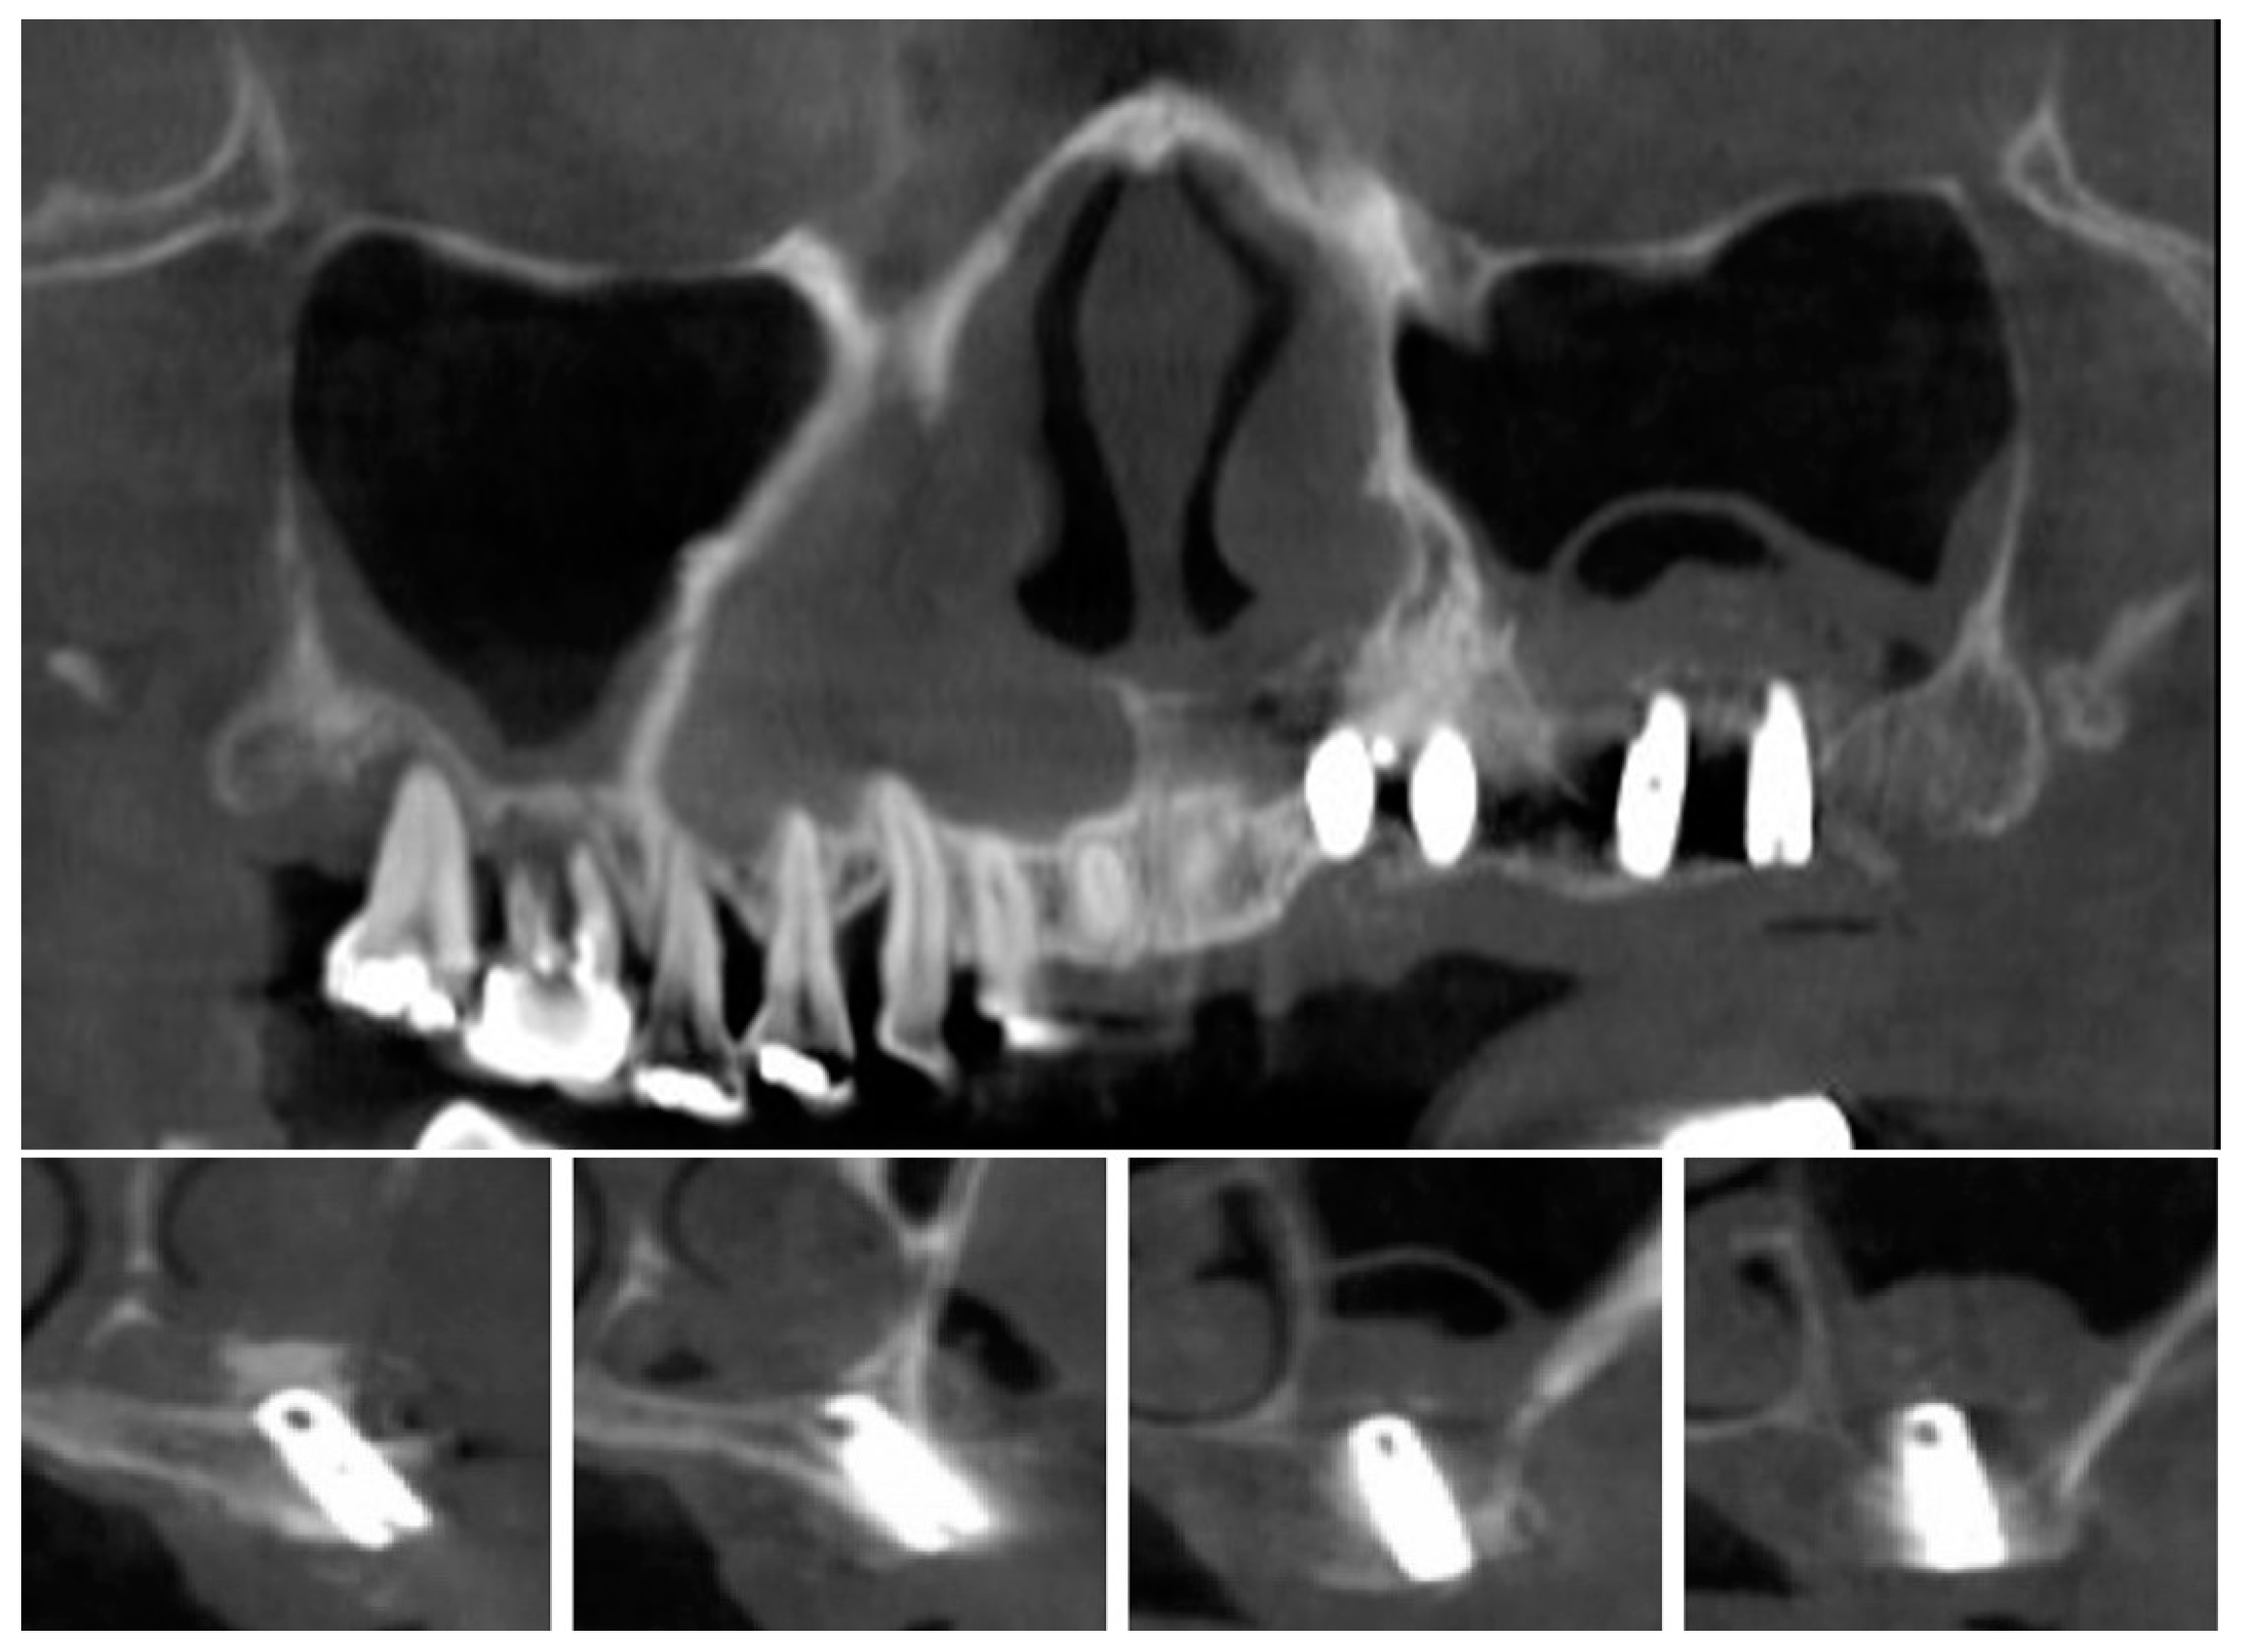

| 1 | #16 | 5 | 12 | 18 | 14 | 9 |

| 2 | #26 | 3 | 18 | 17 | 13 | 10 |

| 3 | #27 | 5 | 16 | 16 | 14 | 9 |

| 4 | #14,15,16,17 | 5,3,5,5 | 22 | 15,18,14,16 | 15,16,14,14 | 10,13,9,8 |

| 5 | #26,27 | 4,4 | 16 | 16,16 | 15,12 | 11,8 |

| 6 | #26 | 6 | 16 | 18 | 20 | 14 |

| 7 | #17 | 2 | 24 | 16 | 15 | 13 |

| 8 | #27 | 2 | 22 | 19 | 18 | 16 |

| 9 | #16 | 2 | 22 | 16 | 14 | 12 |

| 10 | #16,26 | 3,3 | 23 | 23,20 | 20,22 | 17,19 |

| 11 | #26,27 | 3,2 | 24 | 19,18 | 20,16 | 17,14 |

| 12 | #27 | 4 | 22 | 16 | 15 | 11 |

| 13 | #16 | 5 | 12 | 14 | 14 | 9 |

| 14 | #26 | 4 | 16 | 12 | 12 | 8 |

| 15 | #16 | 1 | 20 | 22 | 18 | 17 |

| 16 | #17 | 5 | 13 | 17 | 20 | 15 |

| 17 | #26,27 | 6,6 | 15 | 10,11 | 15,16 | 9,10 |

| 18 | #27 | 3 | 25 | 12 | 14 | 11 |

| 19 | #26,27 | 1,2 | 20 | 21 | 14,14 | 13,12 |